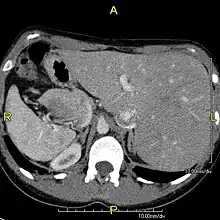

The condition affects all major structures within the thorax and abdomen. Generally, the organs are simply transposed through the sagittal plane. The heart is located on the right side of the thorax, the stomach and spleen on the right side of the abdomen and the liver and gall bladder on the left side. The heart's normal right atrium occurs on the left, and the left atrium is on the right. The lung anatomy is reversed and the left lung has three lobes while the right lung has two lobes. The intestines and other internal structures are also reversed from the normal, and the blood vessels, nerves, and lymphatics are also transposed.

If the heart is swapped to the right side of the thorax, it is known as "situs inversus with dextrocardia" or "situs inversus totalis". If the heart remains on the normal left side of the thorax, a much rarer condition (1 in 2,000,000 of the general population), it is known as "situs inversus with levocardia" or "situs inversus incompletus".

Diagnosis of situs inversus can be made using imaging techniques such as x-ray, ultrasound, CT scan, and magnetic resonance imaging (MRI).[7]